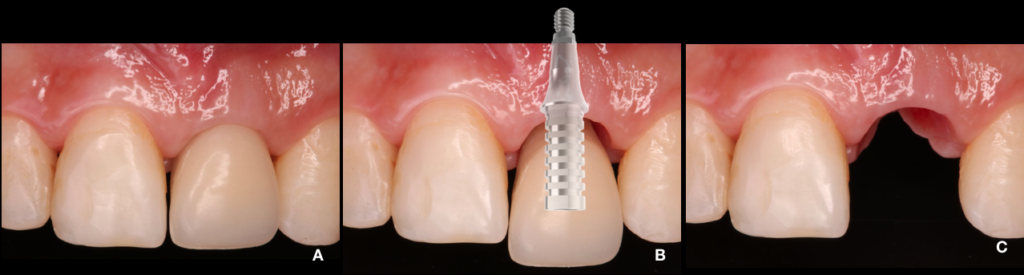

Paciente JCS, sexo feminino, 19 anos foi encaminhada para reabilitação implanto suportada na região do dente 21, a mesma já apresentava implante na região, porém após avaliação tomográfica foi avaliado que o implante presente não possuía osso remanescente ao seu redor e consequentemente estava fibrointegrado. Fig.1

Foi estabelecido tratamento regenerativo prévio (Urban, 2013) (Fig.2/3) com membrana de PTFE-d (Cytoplast TXT250 Vestibular 17mm x 25mm) e posterior instalação de implante do tipo cone morse (Due Cone – Implacil De Bortoli) e tapa implante (Max Cover – 2mm), obedecendo todos os critérios de filosofia de tratamento para tal (Nentwig, 1987). Fig.4A/B

Após 6 meses de regeneração óssea guiada e mais 2 meses de processo de osseointegração tardia do implante, iniciamos a fase de reabertura e manejo do tecido com uma diferente abordagem de técnica de retalho (de Sanctis, 2014) com enxerto de tecido conjuntivo subepitelial (ETCS) removido da porção palatina da região do dente 21 onde havia um volume sobressalente proveniente da ROG, o mesmo foi estabilizado através de um cicatrizador com cinta de 3 mm e sutura colchoeiro horizontal. O manejo do tecido modifica o fenótipo gengival, proporciona estabilidade, reduz a recessão da margem periimplantar, proporciona um melhor contorno da crista alveolar e aumenta a espessura dos tecidos moles (Frizzera, 2018). Fig.5